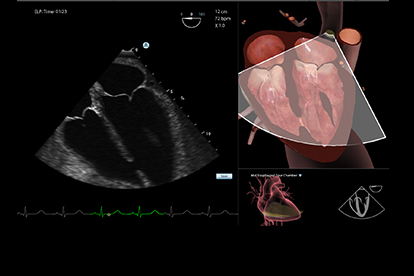

Ultrasound Mentor accelerates the development of basic to advanced technical and cognitive skills, by providing not only the probe manipulation training, but also a didactic environment enabling structured, self-guided learning including step-by-step instructions and educational aids such as 3D anatomical map and probe positioning assistant, all backed up with our progress monitoring tool MentorLearn.

- Advanced diagnostic tools, including Color Doppler, CW, PW, M-mode, and measurements

Bedside Echocardiography Module

Advanced Echo Module

TEE Module

TEE Emergency Module